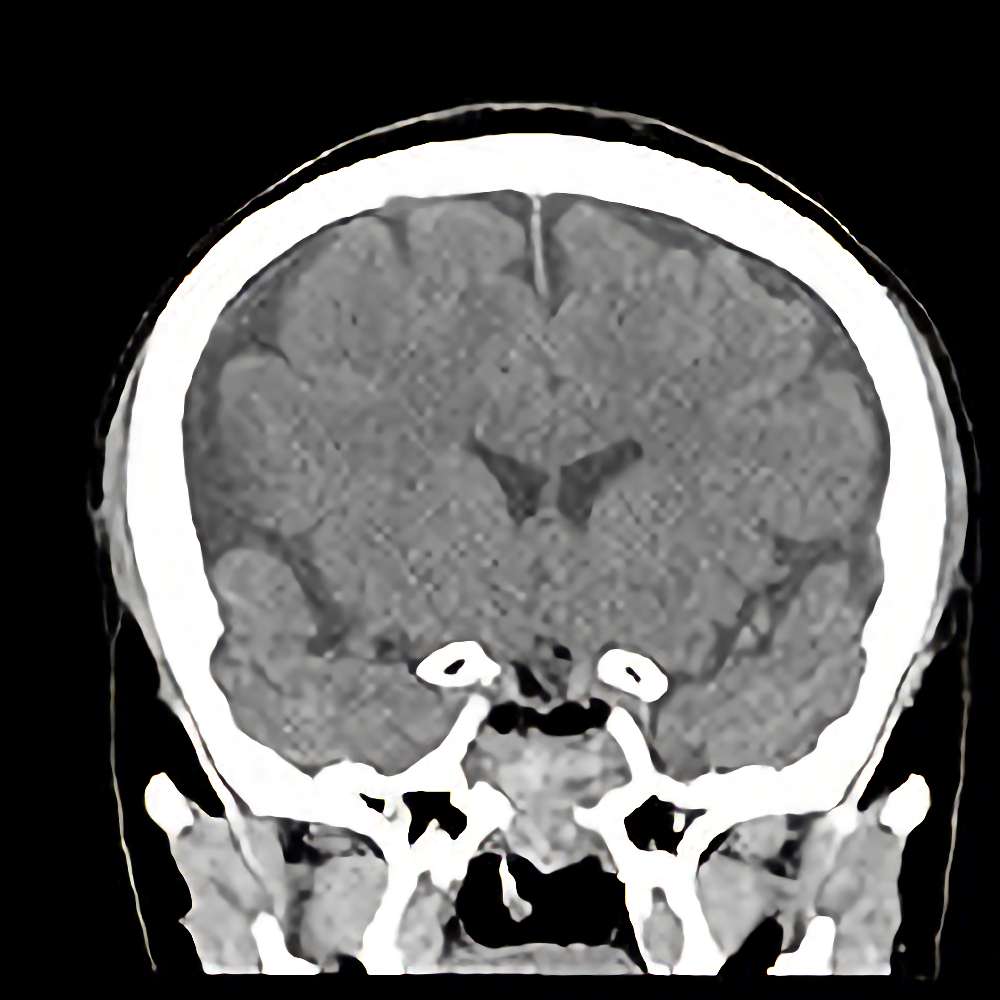

下垂体腫瘍

断層撮影

手術前1

No.’13_48 手術前1

No.’13_48 手術後